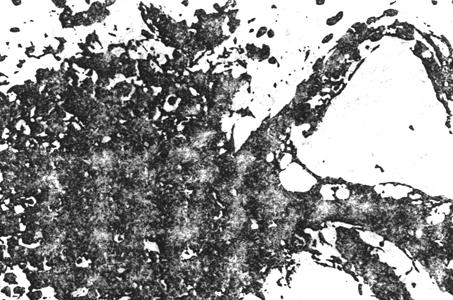

①正常睾丸组织:正常睾丸的曲细精管内可见正在进行分化的各级生精细脆,约5~6层,排列紧凑,规则,以基层膜列管腔依次是精原细胞,初级精母细胞,次级精母细胞,精子细胞和精子。此外还有支持细胞,其体积较大,胞体以基底膜一直伸到管腔。曲细精管之间是间质内有成堆的间质细胞。

图8-3-3 正常人睾丸活检图象